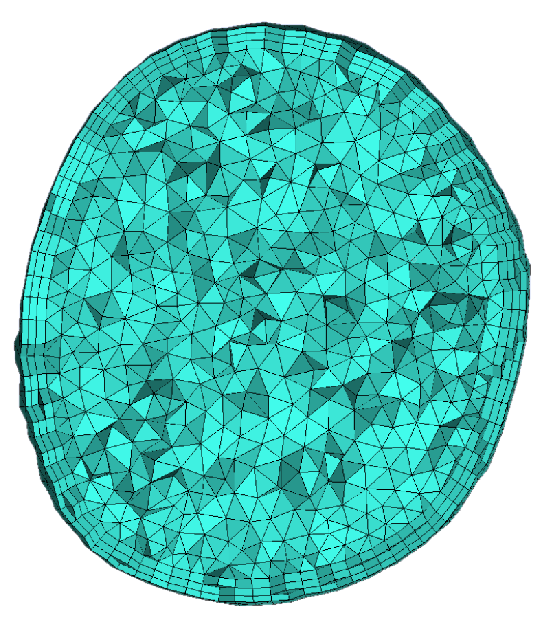

2. Materials and Methods